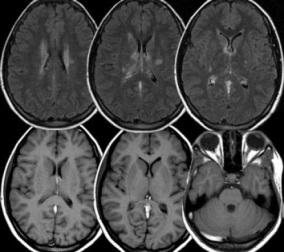

Traditional medicine also uses tools such as acupuncture, cupping therapy, and herbal medicine. TKM practitioners used to make diagnosis by using traditional methods of observing, touching, and smelling. (Sung et al., 2018) TKM doctors now have started to use electroacupuncture devices and pulse wave analysers. Additionally, TKM doctors also started to use modern biomedicine devices like X-ray machines and CT scanners along with traditional medicine tools. In 2012-2016, the most used medical devices of TKM practitioners were MRI and CT scanners and X-ray machines. (Sung et al., 2018) These modern medical devices are helpful in giving objective information for healthcare practitioners. (Sung et al., 2018) However, these devices are not permitted for TKM practitioners to use. This contrasts with China, TCM uses conventional medicine and modern biomedicine devices alike licensed medical doctors. (Sung et al., 2018) There are also no laws preventing the use of modern medical devices and western biomedicine by TCM practitioners. Due to this, studies have been made using both TCM with medical imaging devices. (Sung et al., 2018)

Translating TKM to bioscience

A frequent argument use against TKM is that it is unscientific and TKM physicians are usually marginalised and discriminated in the medical and science community. (Kim, 2007) This led to TKM physicians’ interest in trying to scientifically validate TKM by reconstructing and translating it to laboratory science. (Kim, 2007) Director Ho-Cheol Kim supported the scientisation of TKM and wanted to oppose the discrimination and use science to further develop TKM. (Kim, 2007) Thus, Dr. Kim led the research on TKM experimentation on the condition of Joong-Poong, roughly be described as brain ischaemia. The research focused on verifying the neuroprotective effects of herbal medicine. (Kim, 2007) However, the lab faced many difficulties such as the ambiguous causes of Joong-Poong were too hard to test. One example is that they were scientifically unable to test ‘Internal wind’. Joong-Poong was later equated to cerebral ischaemia, but this conclusion would then transform the meaning of Joong-Poong that was described in TKM classics. (Kim, 2007)